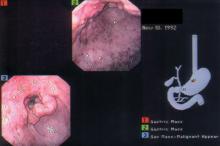

Difficulty eating

The biopsy revealed that the patient had an adenocarcinoma.

The median age at diagnosis is 70 years and median age at death from gastric cancer is 73 years. High rates of stomach cancer occur in Japan, China, Chile, and Ireland. Eighty-five percent of stomach cancers are adenocarcinomas; 15% are lymphomas and GI stromal tumors.

Most tumors are thought to arise from ingestion of nitrates that are converted by bacteria to carcinogens. Sources include foods that are dried, smoked, and salted. Helicobacter pylori infection may contribute to carcinogenicity by creating gastritis, loss of acidity, and bacterial growth. Two important prognostic factors are depth of invasion through the gastric wall (less than T2 [tumor invades muscularis propria]) and the presence or absence of regional lymph node involvement.

In this case, liver metastases were found and the patient decided to not undergo chemotherapy. He died at home after 6 months of hospice care.

Figure courtesy of Michael Harper, MD. Text for Photo Rounds Friday courtesy of Richard P. Usatine, MD. This case was adapted from: Smith, M. Gastric cancer. In: Usatine R, Smith M, Mayeaux EJ, et al, eds. Color Atlas of Family Medicine. 2nd ed. New York, NY: McGraw-Hill; 2013:371-376.